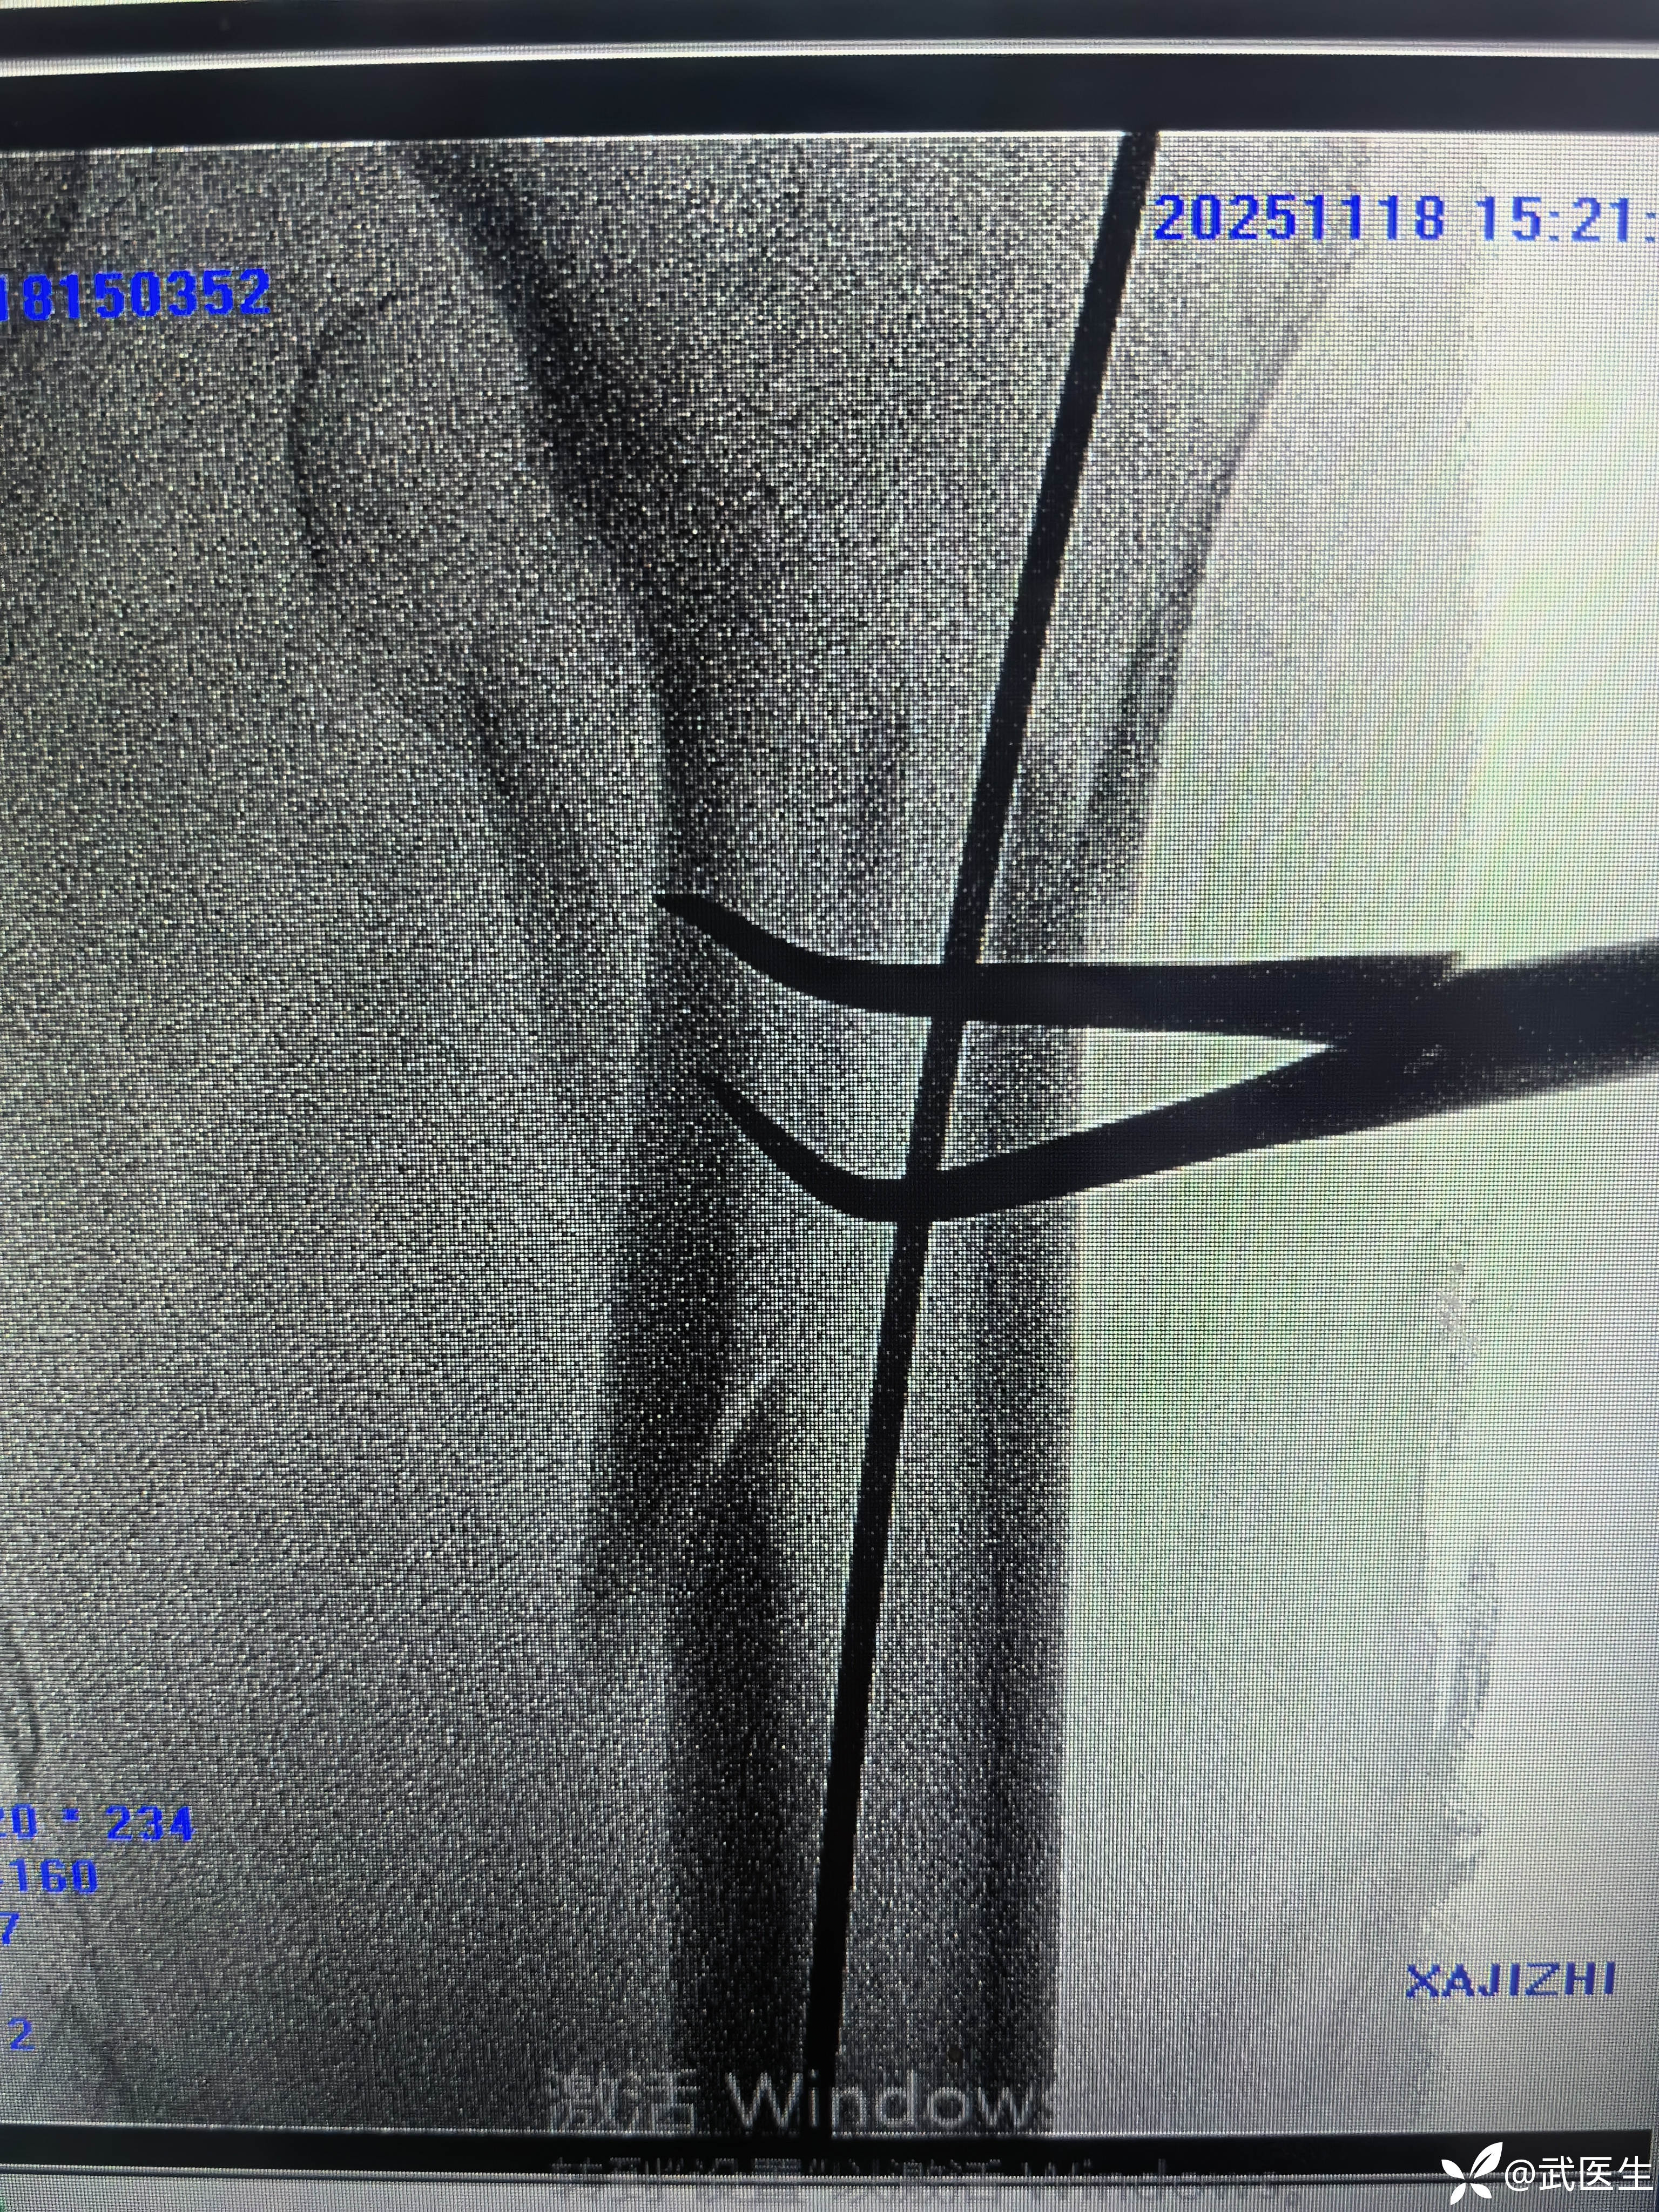

定位透视如下

轴位定位克氏针略偏后

正位还行,调整轴位克氏针定位